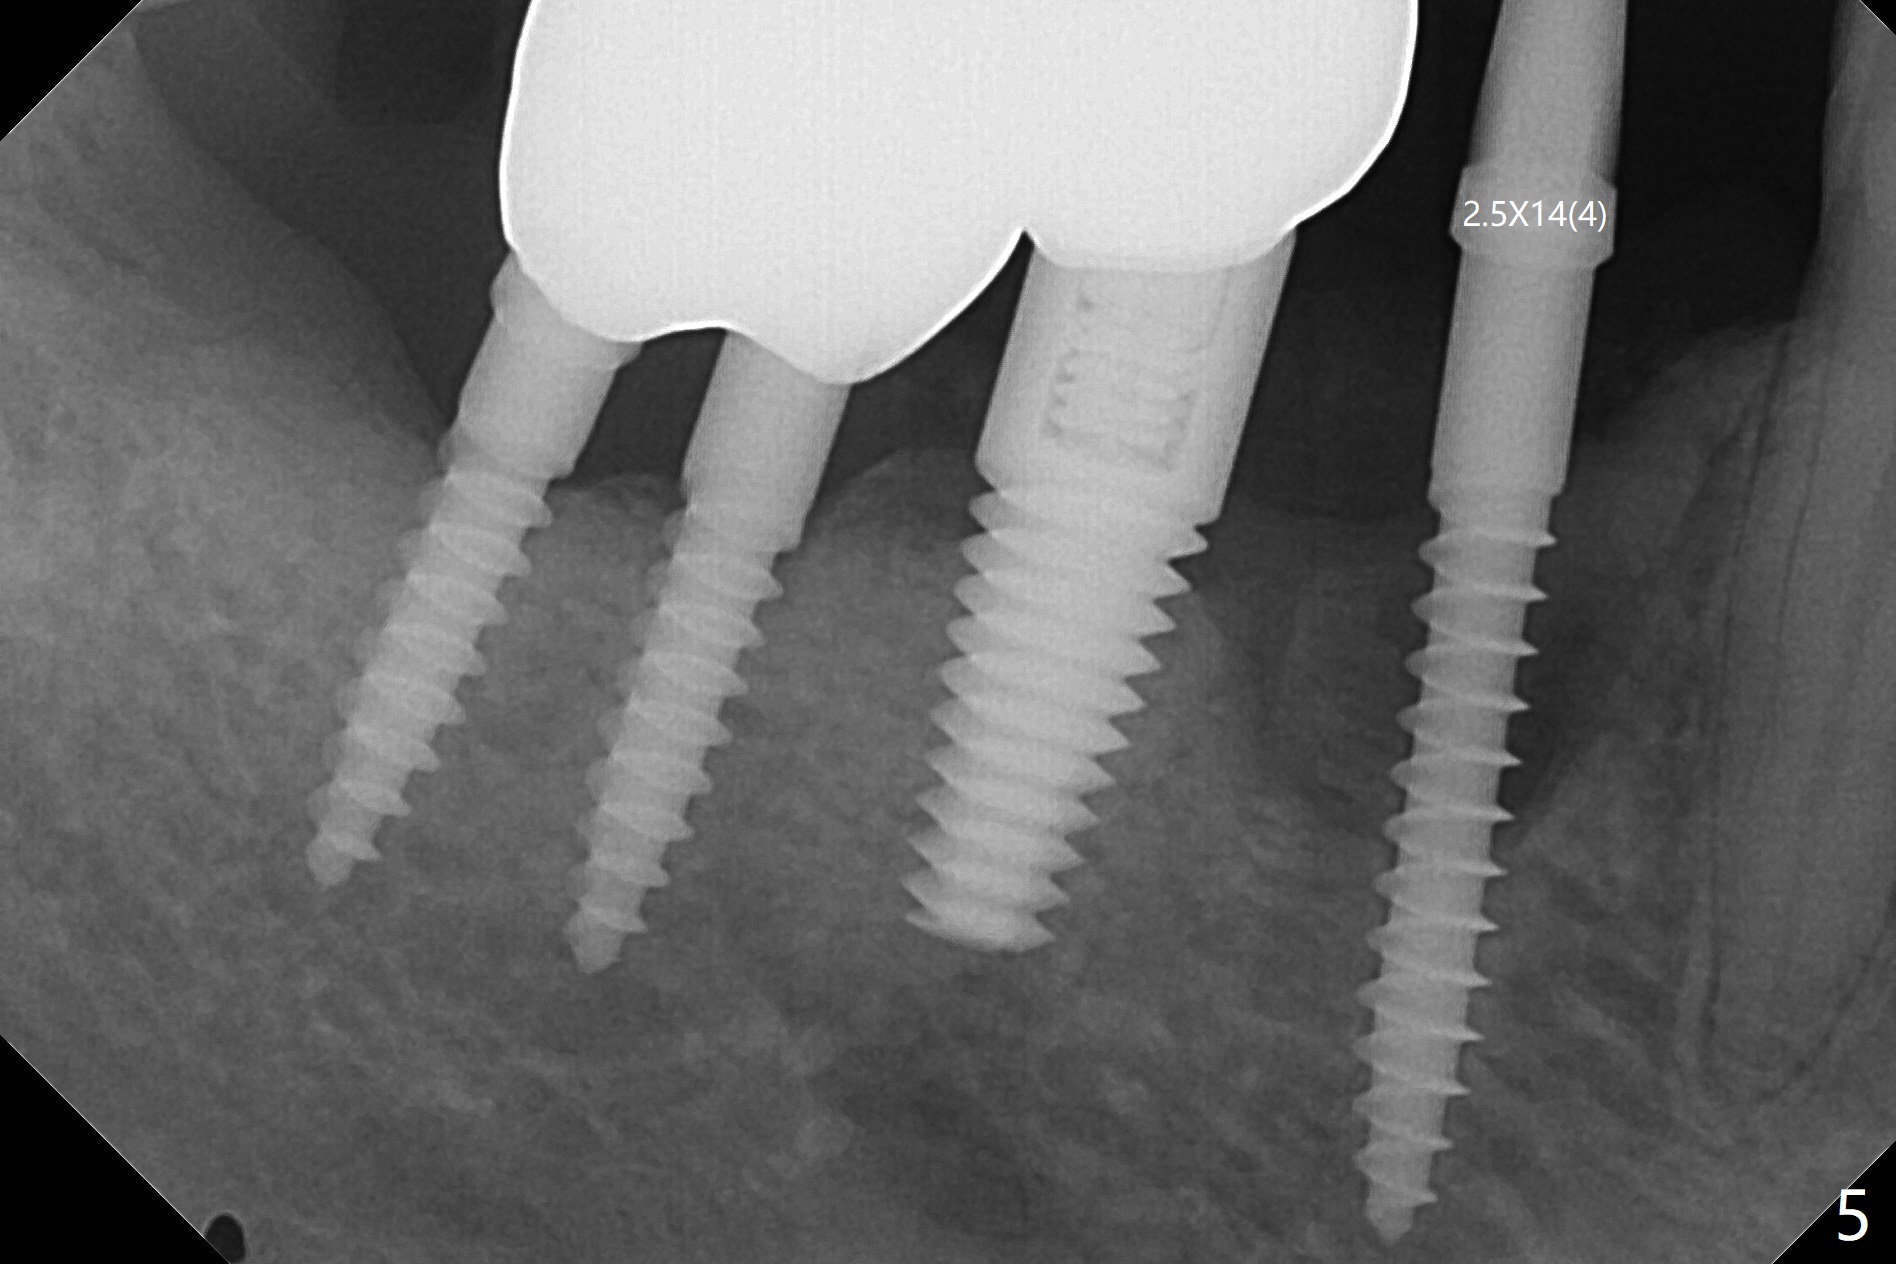

61岁女右下4(粘固后5.5年)植体周围炎(颊侧牙龈没有角化龈(图一:*)),因为颊侧种植(图二),翻瓣证实(图三),取出4.5毫米两段式植体,在舌侧骨质(图四:L)即刻植入2.5毫米一段式植体(图五),颊侧缺损植入大量粘性骨粉(图六:*),覆盖PRF膜后,缝合(图七),与图二对比,窄植体明显舌侧移位。术后一个月撤除牙周敷料(图八),并没有马上制作临时牙冠,让病人容易搞好局部卫生,促进伤口愈合(图九),术后三个月塞入龈线(图十:^),制备基台,植体在牙槽嵴中性位置(颊舌侧),但愿颊侧有足够再生骨质,覆盖植体螺纹。